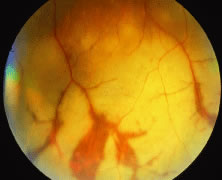

CMV retinitis was first described in 1959 by Foerster.56 Since then it has become obvious that a characteristic retinitis occurs in neonates with cytomegalic inclusion disease and in CMV-infected immunocompromised persons. In transplant patients, CMV retinitis may be the initial clinical manifestation of life-threatening viremia and indicates the need for immediate aggressive lifesaving intervention. For AIDS patients, CMV retinitis often is documented after other opportunistic infections, typically when the CD4 lymphocyte count falls below 100; however, CMV retinitis as the initial manifestation of AIDS has been well described.57 Early retinitis may present with small white lesions that may be confused with cotton-wool spots. However, unlike cotton-wool spots, which are seen in the nerve fiber layer, CMV retinitis is seen as granular whitening located deeper in the retina (Figs. 7, 8, and 9). These same areas of retinitis are often associated with intraretinal hemorrhage and vasculitis of nearby retinal vessels. Although the lesions of CMV retinitis are located in the posterior pole more often than in ARN, peripheral retinitis is not uncommon.58 The lesions can be multifocal as well, pointing out the need for thorough examination of the entire peripheral retina. The vitreous may be relatively quiet allowing excellent visualization of the underlying retina; however, significant vitreitis may occur. The pars plana is relatively spared,54,59 although it is unclear why this should be so, because the pars plana epithelium and the retina share a common neuroectodermal origin. On occasion, stellate keratic precipitates with cell and flare can be observed on the cornea and in the anterior chamber. In some cases a prominent retinal vasculitis may be seen posterior to the area of retinitis (Fig. 10).

Progression of the retinitis generally occurs with a leading edge of active retinitis and a trailing region of thin gliotic retina. This pattern indicates cell to cell transmission of the virus. CMV is a slowly progressive, necrotizing retinitis that may affect the posterior pole, the peripheral retina, or both and may be unilateral or bilateral. Involved areas appear as white intraretinal lesions; areas of infiltrate; and often necrosis, along the vascular arcades in the posterior pole. In addition, prominent retinal hemorrhages are often seen within the necrotic area or along its leading edge (Figs. 12 and 13). Peripherally, CMV retinitis tends to have a less intense white appearance, with areas of granular, white retinitis that may or may not demonstrate associated retinal hemorrhage (Fig. 14). As the retinitis progresses, an area of atrophic, avascular retina may remain with underlying retinal pigment epithelial atrophy and/or hyperplasia (Fig. 15).57,58,60,62 Peripheral CMV retinitis may be the most common form of CMV retinitis seen. Patients may initially complain only of floaters with or without a visual field deficit.57 Wide-angle fundus photography and fluorescein angiography may be of benefit when the diagnosis is uncertain. These techniques may be used to document progression of retinitis, and fluorescein leakage in areas of retinitis may be helpful in confirming the diagnosis. Although peripheral CMV retinitis may not pose an immediate threat to vision, initiation of treatment should be seriously considered because several investigators have shown that untreated CMV retinitis is inexorably progressive and becomes bilateral in virtually all untreated patients.59,60,65,74–76 Occasionally, noncontiguous areas of new retinitis may be seen. As healing takes place, a thin glial scar replaces the necrotic retinal tissue. The transition from infected to noninfected retina is usually sharply demarcated and well seen during the active phase of the disease. When healing takes place, the transition zone is between a glial scar and normal retina and may be difficult to visualize. Clinically, the pigment epithelium tends to develop a characteristic spiculated granular appearance directly under the residual glial scar. The retina in the immediately adjacent uninvolved areas is thick in comparison to the glial scar, thus, differing light reflexes occur with indirect ophthalmoscopy. Using the pigment epithelium pigment changes and light reflexes, one can define the extent of prior retinal involvement. More importantly, defining the edge of prior involvement allows one to predict with great accuracy the sites of new involvement, allowing for more effective monitoring of therapeutic efforts to control the infection. Other manifestations of CMV retinitis include retinal edema, attenuated vessels, perivascular sheathing, and exudative retinal detachment.77 In addition, vitreitis and anterior uveitis are often seen,70 and optic atrophy may occur as a late manifestation secondary to widespread retinal destruction. CMV may be demonstrated in vitreous biopsy specimens in these patients.65 The yield may be higher in the presence of marked vitreitis because CMV is a cell-associated virus. Other causes of retinitis, including herpes simplex retinitis,78,79 toxoplasmosis,80 Candida, Behçet's disease, syphilis, ARN,7,28,81 and SSPE82 can usually be distinguished from CMV on clinical grounds. Cotton-wool spots are nonspecific and may be seen in diabetes mellitus, hypertension, severe anemia, systemic lupus erythematosus, dermatomyositis, and leukemia,83,84 as well as AIDS. It may be difficult to distinguish a small focus of nonhemorrhagic CMV retinitis from a cotton-wool spot corresponding to the area of peripapillary optic nerve fiber layer that was destroyed (Figs. 16 and 17). In eyes in which CMV infection initially involves the optic nerve head, the visual acuity may be normal early; however, the visual prognosis may be poor because these eyes often go on to loss of light perception (see Fig. 13). When retinitis is in close proximity to the optic nerve head or macula, a serous retinal detachment may be seen that will resolve with therapy.

Fig. 12. A patient with a relatively nonhemorrhagic variant of cytomegalovirus retinitis. Note at the center of the lesion (oldest area of infection) the retina is atrophic and pigmentary changes can be seen. Peripheral to it the retina is edematous, and this is the area of active infection.

Fig. 13. A patient with hemorrhagic variant of cytomegalovirus (CMV) retinitis that affected the posterior pole and optic nerve. Hemorrhages are most often intraretinal, and white areas correspond histologically to intracellular and extracellular edema and necrosis of the neurosensory retina. Eyes with extensive optic nerve involvement secondary to retinal involvement may still retain good central vision unless the papillomacular bundle is involved. When retinitis starts in the optic nerve head, the prognosis for vision is poor.

Fig. 14. Cytomegalovirus retinitis in the periphery may have minimal hemorrhagic components.

Fig. 15. Area of healed cytomegalovirus retinitis showing characteristic pigmentary changes. In the area of retinal necrosis, the retinal pigment epithelium (RPE) is also thinned and bare choroidal vessels are visible.